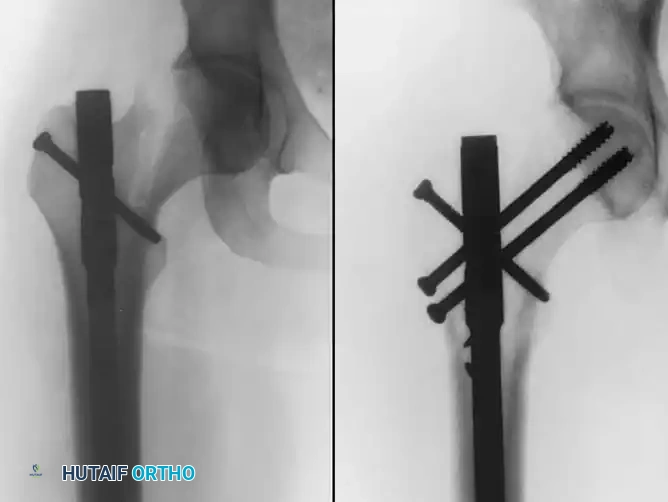

Radiographic sequence showing an ipsilateral femoral neck and shaft fracture. The neck fracture must be stabilized prior to or concurrently with intramedullary nailing of the shaft to prevent catastrophic displacement.

Fixation of a complex proximal femur fracture associated with hip trauma, utilizing a cephalomedullary nail combined with supplementary anterior neck screws for rotational control.